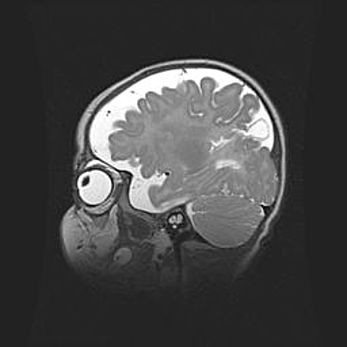

Мальформация Денди-Уокера. Киста задней черепной ямки.

Агенезия мозолистого тела.

Возраст: 2,5 месяца

Вес: 2420 г

Пол: женский

Окружность головы: 37 см

Срок гестации: 32 недели

Мальформация Денди—Уокера — редкий вид патологии ЦНС, представляющий собой врожденный порок развития каудального отдела ствола и червя мозжечка, ведущий к неполному раскрытию срединной (Мажанди) и латеральных (Лушка) апертур IV желудочка мозга. Для этогно синдрома характерна триада симптомов: гипотрофия червя мозжечка и/или полушарий мозжечка, кисты задней черепной ямки, гидроцефалия различной степени. В 70% случаев порок сочетается и с другими аномалиями головного мозга, в частности с агенезией мозолистого тела.